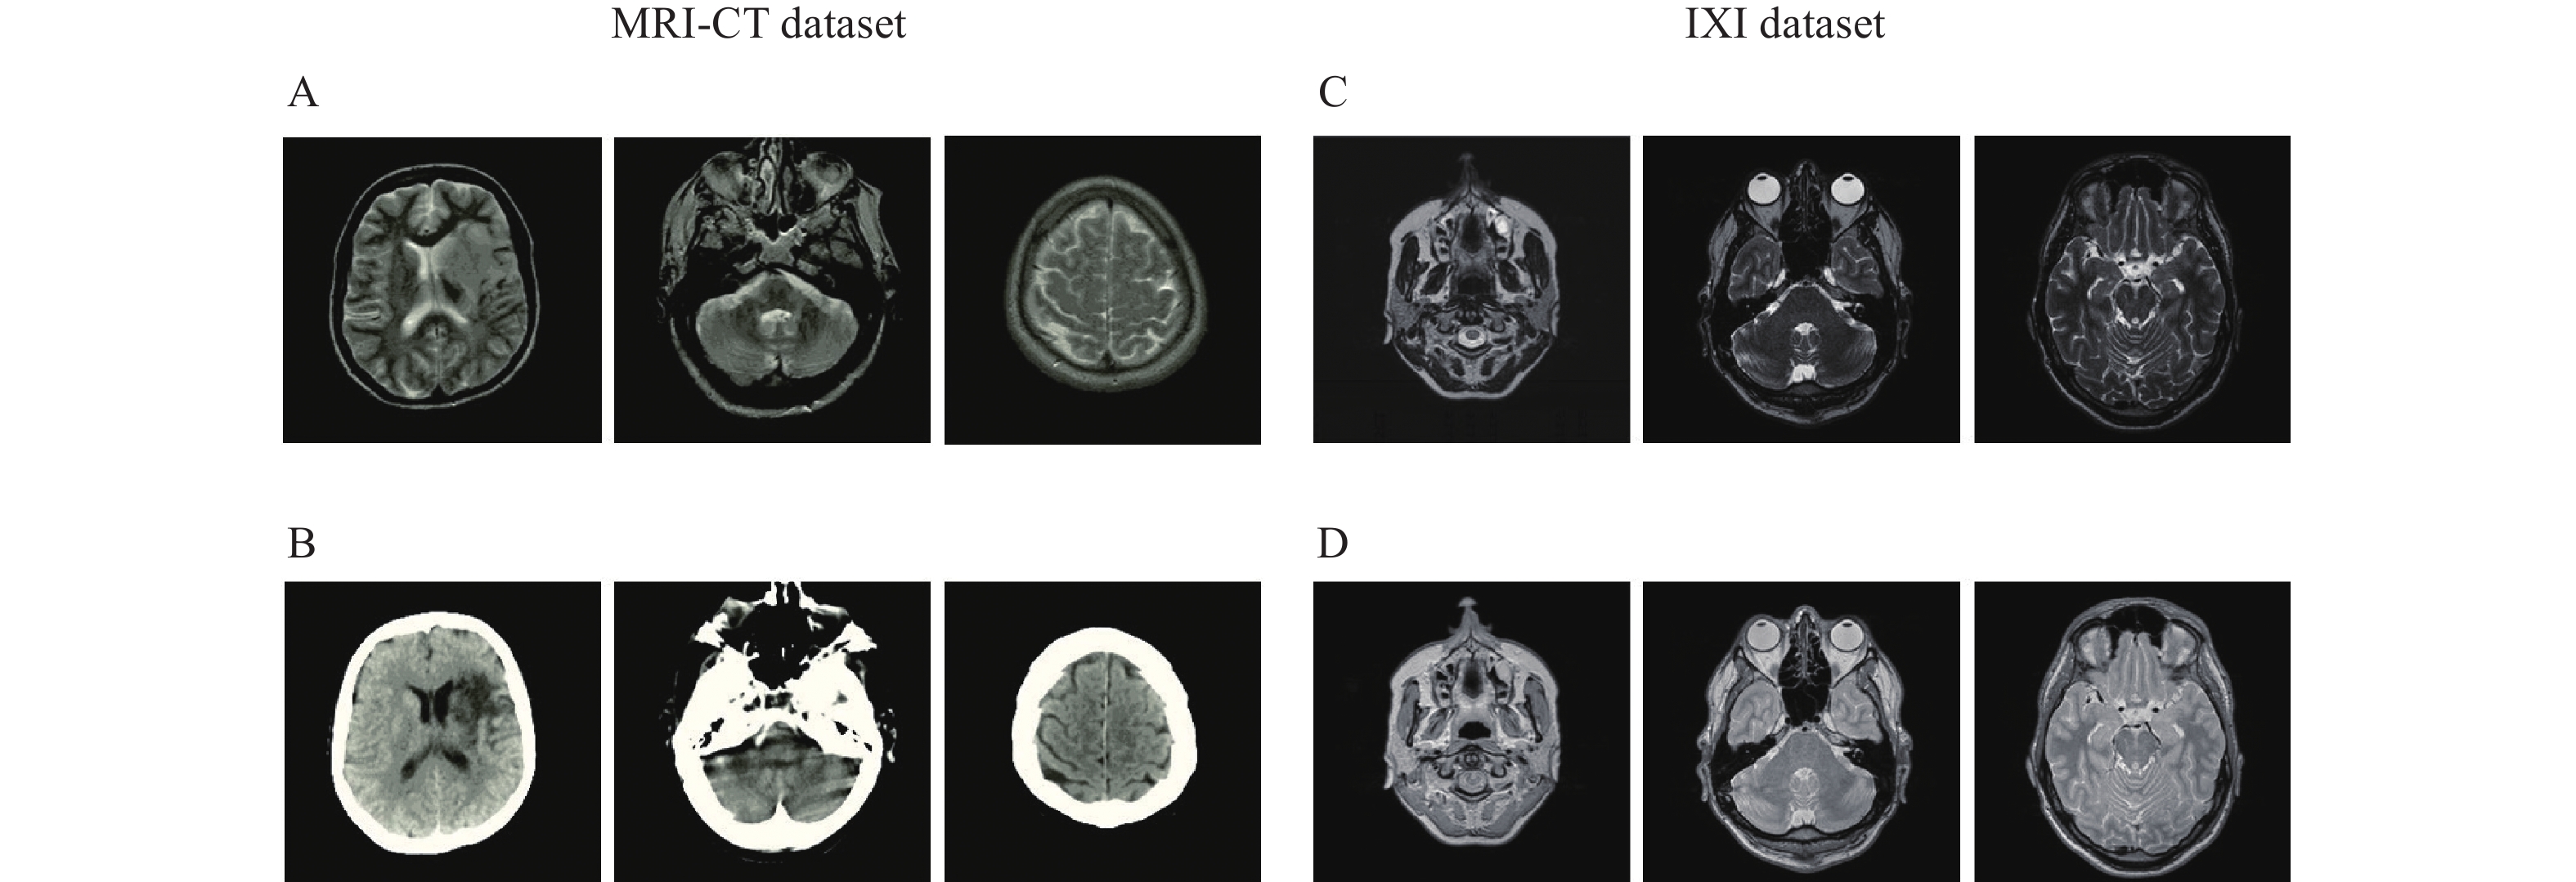

Two datasets are utilized in this study, both of which have CT-MRI and PD-T2 paired data. These were used to analyze the proposed encoder-decoder network for paired data and the proposed EGGAN for unpaired data.

This dataset contains MRIs from 18 patients who were randomly selected. MRIs were obtained using a 1.5 T Siemens Avanto scanner using a T1-weighted 3D spoiled gradient (repetition time 11 milliseconds, echo time 4.6 milliseconds, field-of-view 256×256×160 mm3, and flip angle 20°). Related CT images were obtained using a Siemens Sensation 16 scanner with tube voltage 120 kV, in-plane resolution 0.5×0.5 mm2, exposure 300 mAs, and slice thickness of 1 mm (https://github.com/ChengBinJin/MRI-to-CT-DCNN-TensorFlow).

This dataset contains nearly 600 MRIs from relatively healthy participants, which were collected by three different hospitals in London including the Hammersmith Hospital which used a Philips 3T system, Guy's Hospital which used a Philips 1.5T system, and the Institute of Psychiatry which used a GE 1.5T system. PD and T2 images obtained using the Philips Medical Systems Gyroscan Intera 1.5T have the following parameters: repetition time 8178 milliseconds, echo train length 16, number of phase encoding steps 187, and flip angle 90° (http://brain-development.org/ixi-dataset). PD and T2 images obtained using the Philips Medical Systems Intera 3T have the following parameters: repetition time 5725 milliseconds, echo train length 16, number of phase encoding steps 187, acquisition matrix 192×187, and flip angle 90°. Fig. 5 represents certain samples of the utilized datasets.